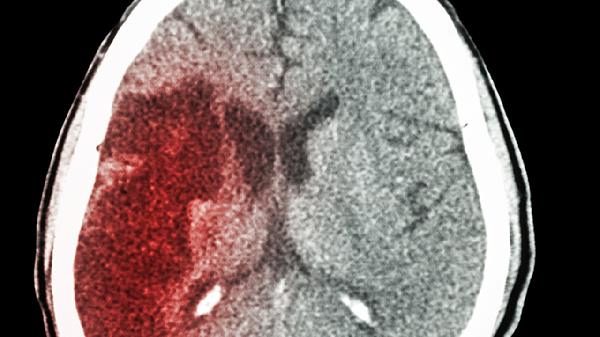

缺血性中风就像身体里的"交通大堵塞",当脑部血管突然被"路障"堵住,脑细胞就会因为"断粮"而罢工。这种危险的状况,往往不是突然发生的,而是多种因素长期作用的结果。了解这些"肇事原因",才能更好地守护我们的脑血管健康。